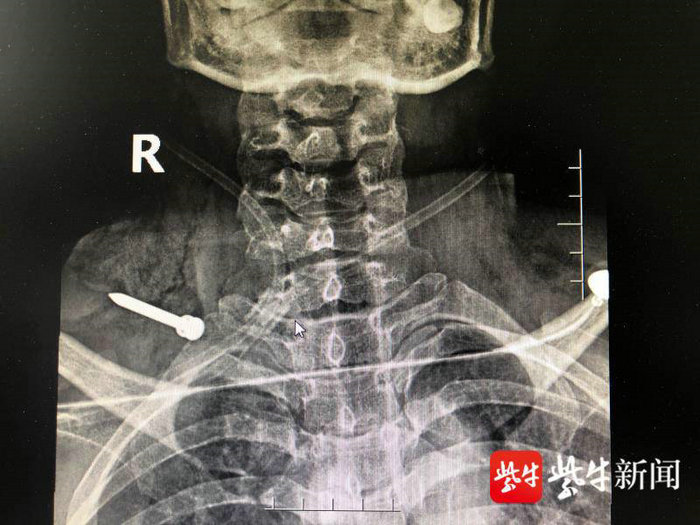

X线检查显示患者体内有根铁钉

经过查体发现,王女士右颈部有一长约6cm的伤口,伤口处还外露着一根铁钉,铁钉尖头朝外,创口内还存在活动性出血,右侧上肢活动受限。影像资料未见明确的颈部骨结构破裂。王奇表示,需立即进行颈部手术探查,明确损伤情况,取出异物。